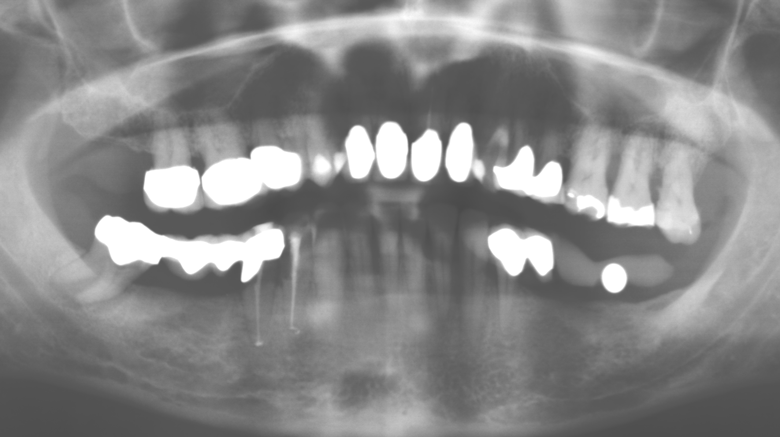

Im Rahmen der ZehnJahresKontrolle zeigten sich keine Hinweise auf einen fortschreitenden parodontalen Attachmentverlust oder einen periimplantären Knochenverlust (Abb. 3).

Für den klinischen Langzeiterfolg des parodontal kompromittierten Patienten ist die standardisierte und regelmäßige risikoadaptierte Betreuung im Rahmen der UPT der zentrale Baustein des Behandlungserfolgs. Dies gilt in besonderer Weise für Patienten, die nach erfolgreich abgeschlossener parodontaler Sanierung mit Implantaten versorgt wurden (Abb. 11a und b).